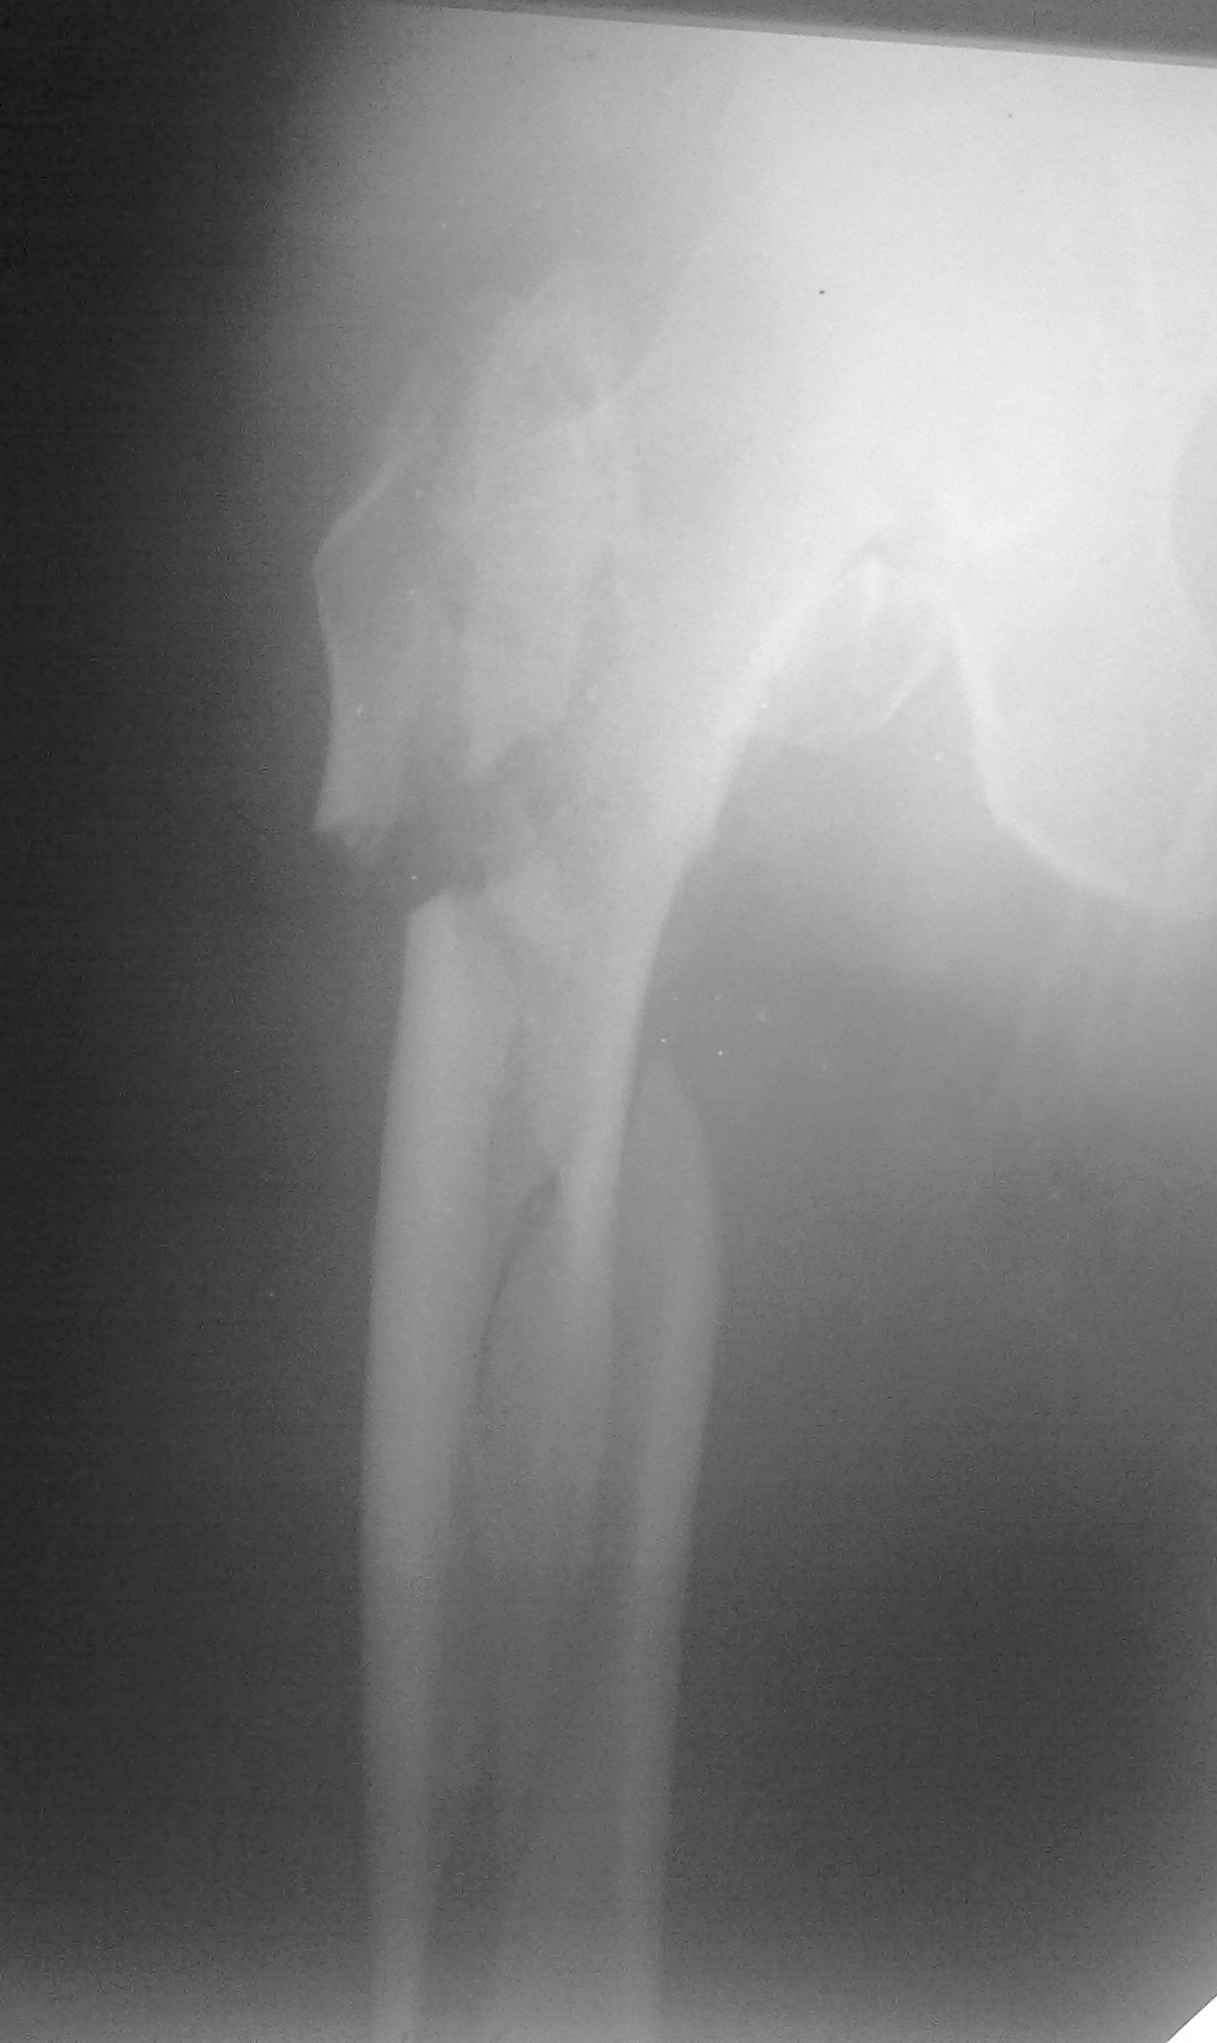

Пациент 83 года. Реконструктивный бедренный стержень Chm